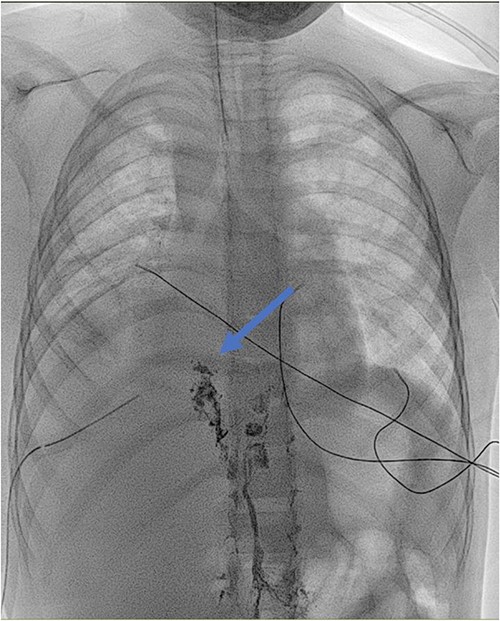

Antibiotic therapy and parenteral nutrition were initiated. In addition, Sandostatin was started at a dose of 1mcg/kg/h. Primary workup lymphoscintigraphy showed no lymphatic leakage or lymphatic abnormalities (Fig. 1). Examinations addressing malignancy and other causes of chylothorax did not reveal any additional pathologic findings. After 14 days of conservative treatment, the patient showed no significant improvement with a pleural fluid production of over 500 cc/24 h. Therefore, it was decided to perform an exploratory thoracoscopy with the injection of indocyanine green. The thoracic duct was visualized during the procedure but showed no active leaks. A pleurodesis was performed. After surgery, there was an improvement with decreased pleural fluid production. Medium Chain Triglyceride (MCT) diet was introduced, and somatostatin was slowly reduced. Unfortunately, after 4 days, the patient reacquired a significant amount of pleural fluid. The thoracic duct was clipped, and a lung biopsy was performed due to the lack of improvement. Clinically, the patient progressed inconsistently with a further episode of vomiting, which resolved spontaneously. The thoracic tube was removed 10 days after the second intervention. Follow-up radiographs showed the return of pleural effusion with the incomplete collapse of the lower lobe. A lymphangiography confirmed the excellent positioning of the clip and could not find any other abnormalities or leaks (Fig. 2). The genetic and anatomopathological study did not show any irregularities. Four months after discharge, the overall condition of the patient was good.

Lymphangiography: detection of lipiodol in the ductus thoracicus (blue arrow). The marker stops at the clipping of the ductus thoracicus. No leakage is detected.